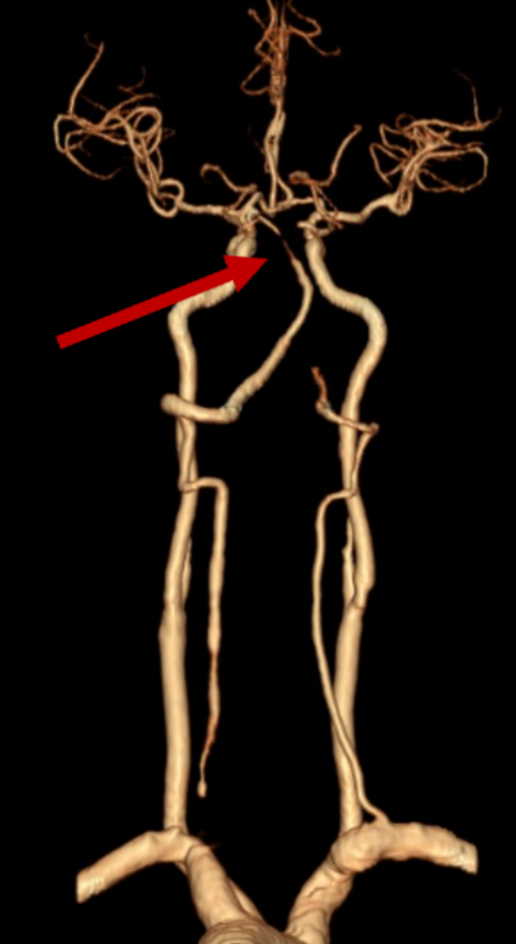

何旭英主任以及卢海克副主任医师通过脑血管造影,发现唐先生的脑血管状况非常差,手术难度高,右侧椎动脉先天发育不良,未汇入基底动脉,左侧椎动脉竟然也闭掉了。

“血管上不去,就没法做手术,更挽救不了患者的生命。”脑血管病介入团队当机立断,没有路也要开一条路出来,经过努力,开通了闭塞的椎动脉,并植入了支架保障血管持续的通畅性,再进一步将取栓器械直达基底动脉。